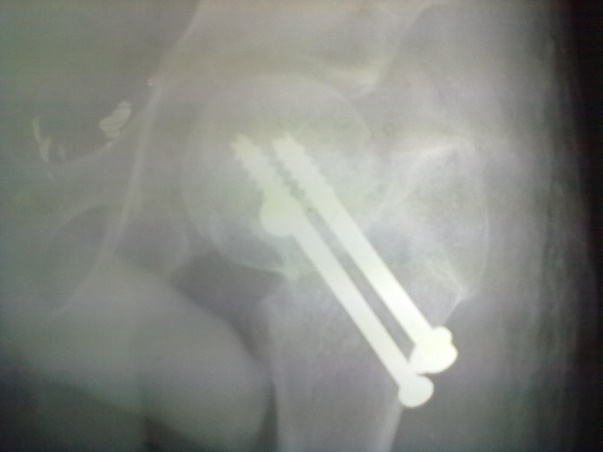

Sixteen patients of ununited fracture neck of femur (presenting late i.e. more than 3 weeks) in the children and adolescent were treated with quadratus femoris based muscle pedicle bone graft with internal fixation between 2004 to 2019. Pathological fracture, recent fracture and compound fracture were excluded from study. Mean age was 14.25 years (standard deviation 1.27 and range 12 to 16 years). Boys dominated our series (n=10 i.e. 62.50%) and right side was more commonly involved (n=12 i.e.75%). All of them were investigated for their fitness for spinal block or general anaesthesia. Steps of procedure including patient positioning, surgical procedure, provisional fixation and definitive fixation were discussed and documented. Radiographic evaluation included A-P View in 15 degree internal rotation, and Lateral view. Average delay in presentation was 5.88 weeks (range was 3-10 weeks). We had 02 transepiphyseal, 11 transcervical and 3 cervicotrochanteric fracture in our series. All the fractures were displaced and having some absorption of femoral neck.

Spinal block was used in the procedure. Prone position on fracture table with radiolucent top was used. Fracture site was exposed through posterior approach and sclerosed margins of the fragments were freshened. Fracture was reduced with appropriate neck shaft angle and fixed with Moors pin/ knowels pin or 4 mm /7mm partially threaded cancellous screws. Any rotation or tilt was corrected. The fixation was augmented with quadratus femoris muscle pedicle bone graft harvested from intertochateric crest area with a bone pedicle of length 2 cm, width 1 cm and depth 1 cm. The graft was secured to the proximal femoral head fragment with 3.5mm cortical screw or 4mm cannulated cancellous screw. Soft tissue closure was done over drain.

Patients were followed up at 2 weeks, 4 weeks, 6 weeks, 8weeksk, regularly at 6 week interval for next 6 month and then at three month interval up to two year. Radiographic analysis was performed at each follow up with special attention to extent of callus formation, alignment of fragments and hard ware integrity.